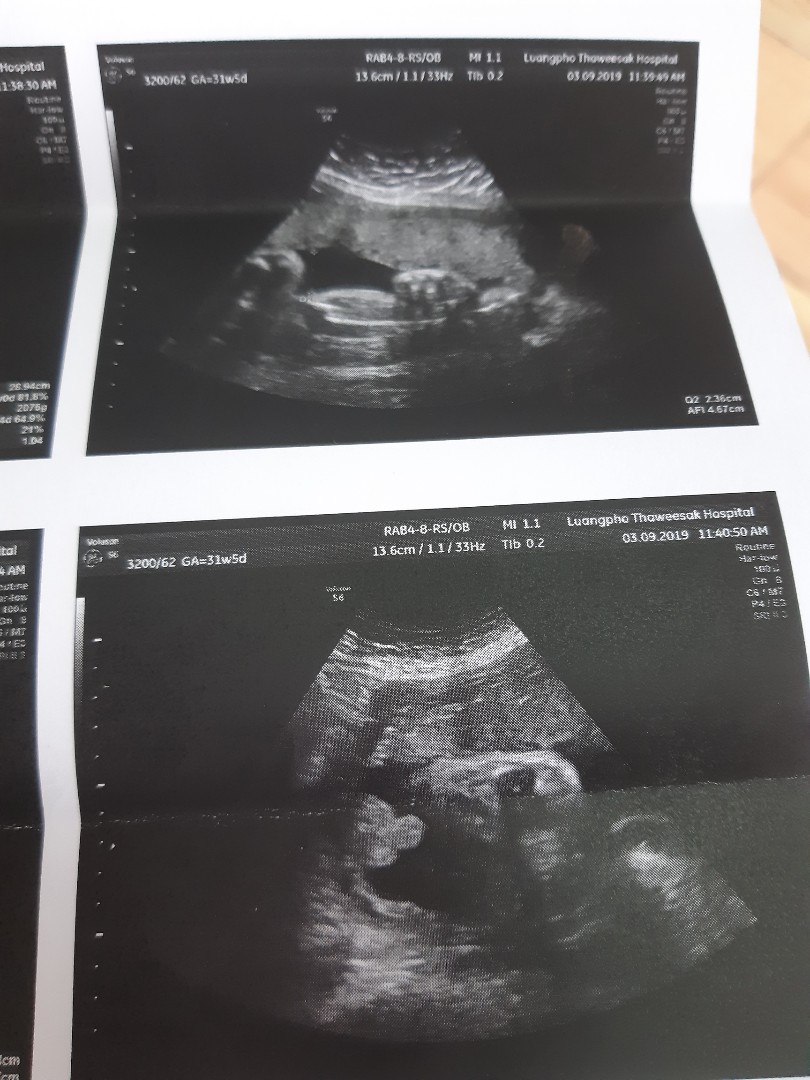

โชว์ผลซาวด์กันค่ะ

คุณลุงหมอบอกมีกลีบ?ใครมีกลีบ ใครมีแท่ง ลงมาอวดกันจร้า

ลูกสาวจ้า ชัดมาก

มีแท่งคร่าบบบบบ

หมอบอกผู้ชายค่ะ

เรามีแท่งน้อยๆ 56

จู๋ ..ทั้งคู่ครับ

ผมมีเเท่งคับ🤣🤣

กำลังตั้งครรภ์